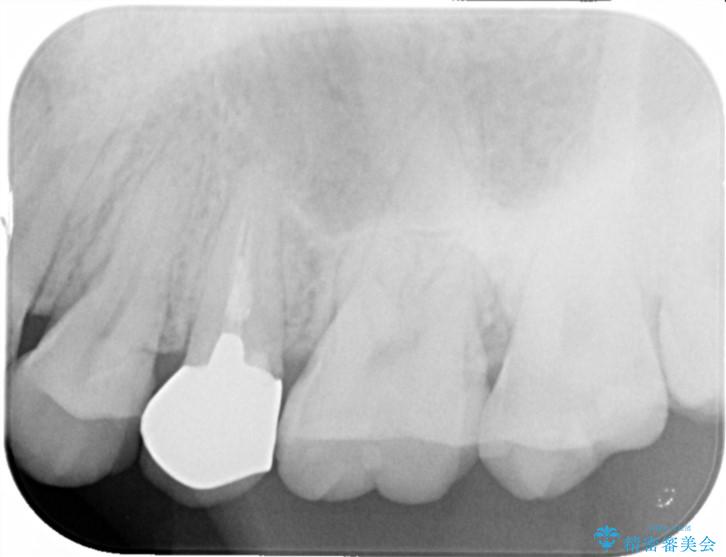

- 歯ぐきの腫れや、歯の内部が黒く見えることからの虫歯の治療を求めて来院されました。

虫歯が大きかったことから、神経の温存はできたものの歯ぐきよりも深い虫歯の問題を解決するため部分矯正治療を併用したセラミック治療を行うこととしました。

当初、歯ぐきよりも深い虫歯のぞんざいや、歯のポジションに問題がありましたがマルチブラケットを用いた部分矯正を行うことで適切な位置へと歯を移動させ、歯周環境を整えたセラミック治療を行うことができました。